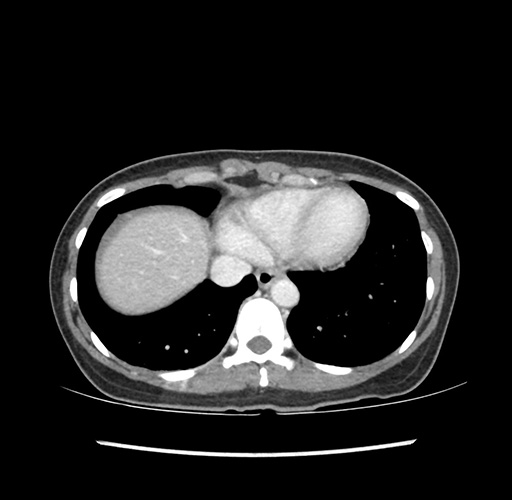

Imaging Analysis

Look through the patient's CT scan to identify any areas of concern for the necessary procedure.

Based on your CT findings, which issue(s) would give reason for "planned slowing down moment(s)" in this case?